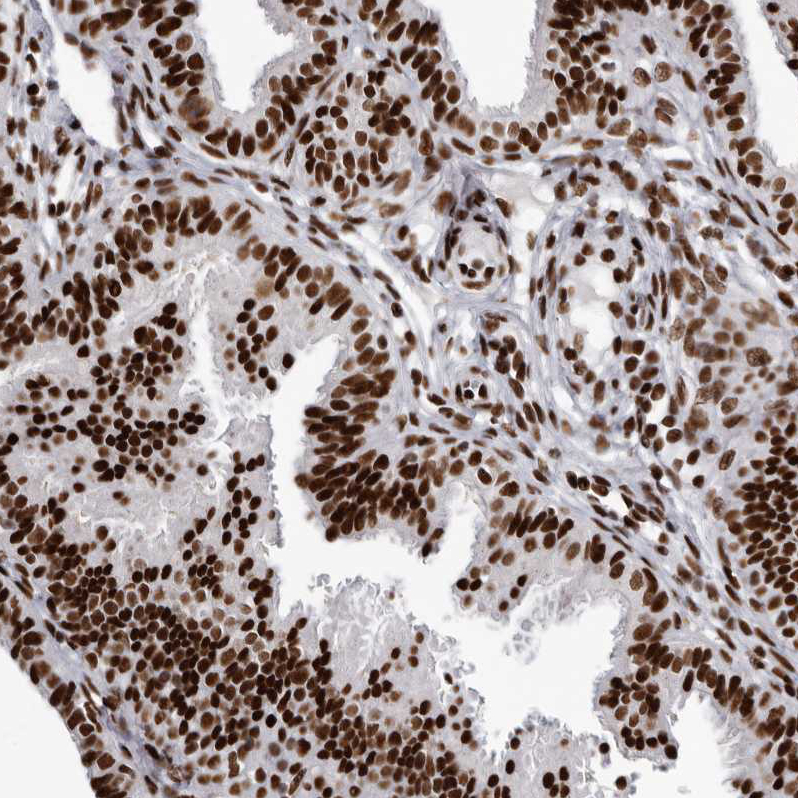

Immunohistochemical staining of human fallopian tube, gastrointestinal, kidney and lymphoid tissues using Anti-NUMA1 antibody HPA029912 (A) shows similar protein distribution across tissues to independent antibody HPA019841 (B).